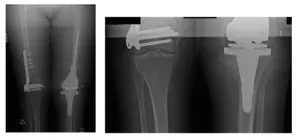

Patient is an 80 year old female who had come in from out of state after being advised to receive an amputation of her left leg. Patient previously had 5 surgeries, including irrigation, debridement, and drainage of her left knee after she was involved in a car accident several years ago. Previous surgeries were performed by anout of state facility.

Patient came in with X-rays to review, as shown below. Upon examination, patient was experiencing pain and was ultimately advised to receive a left staged Total Knee Arthroplasty (TKA) Reconstruction surgery. All alternatives and options were discussed at length with the patient.

It was explained to the patient that she had a comminuted fracture in which the bone broke into many pieces and that the two options were an Open Reduction Internal Fixation (ORIF) procedure or a replacement, but was advised that the replacement was the better option to achieve better results.

X-Rays show osteolysis of the femoral and tibial component of the left TKA prosthesis

There is also capsular calcification and capsular distention along with severe thinning of the cortex around the upper aspect of the femur. Arrows show osteolysis of the bone.

Pre-operative Scanogram show mild degenerative changes at both hips and right knee

There is an orthopedic plate and multiple screws in the right distal femur.